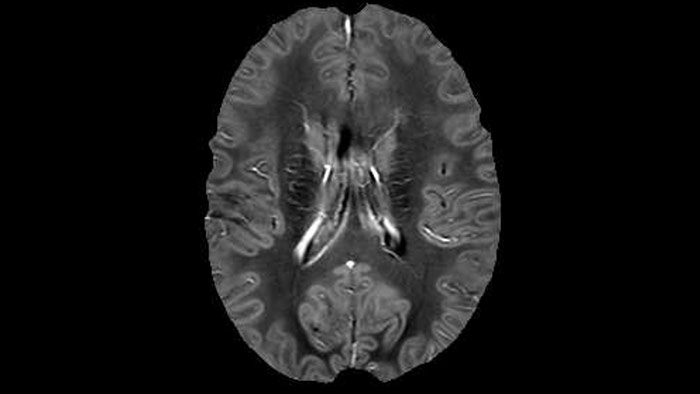

“In addition to traditional imaging like FLAIR for lesion identification, we see a real push towards techniques that weren’t normally required for MS, including good highresolution 3D T1 weighted images to do volumetrics. We’ve also started looking at spinal cord imaging again, since techniques have improved in terms of acquisition and analysis. Another important technique is susceptibility weighted imaging (SWI), particularly if we are looking for central veins in lesions, which is extremely helpful for diagnosis.”

of limiting MWI to the brain, even without the cerebellum, we can now spend about the same amount of time and scan the whole brain and the cervical spinal cord, which is a huge boost for us.” Dr. Rauscher says, “For MWI we perform 3D T2 with 32 or more echoes. This used to take a long time, but with Compressed SENSE we can decrease this to ten minutes for the whole head. Because of the large field of view (FOV) on the readout direction, we even get information from the brainstem, which we previously missed when we were using the GRASE approach. Having the whole head scan is nice because it has spatial resolution, orientation and FOV that are comparable to the standard 3D clinical MS scans, including the FLAIR and 3D T2, and a 3D T1 for brain volume.”

Dr. Rauscher says, “With better gradients we can use a shorter echo spacing on the spin echo, so we get better sampling of the rapidly decaying myelin signal, which typically has T2 of around 10-20 milliseconds at 3 Tesla. If we can reduce echo spacing from about 8 to 5-6 milliseconds, we get a much better sampling of the short decay component and increase our SNR, which is a big advantage. The same is true for multi-echo gradient echo which we use for susceptibility mapping and for mapping venous vessels in MS.”

Accelerating scans helps researchers achieve their imaging goals

He says the accelerated scanning is achieved via the use of Compressed SENSE and MultiBand SENSE. “We can use Compressed SENSE acceleration factors of about 10 on a 3D FLAIR for instance, which is quite remarkable compared with what we saw with the Achieva. With 3D FLAIR, we can push the spatial resolution to 0.3 cubic mm and it works. Previously, our 3D FLAIR scans lasted about 8 minutes, but now with Elition they are five minutes. The SNR is also visibly better. Our SWI and QSM scans look fantastic. Also, since a lot of neuroimaging is EPI based, using the MultiBand SENSE technique can increase temporal resolution and make it possible to run complicated DTI scans relatively quickly.”

Sagittal 3D FLAIR with 0.3 mm3 voxel volume acquired in 5:12 min. using Compressed SENSE showing a (juxta)cortical MS lesion.

QSM based on a Compressed SENSE multi-echo SWI.